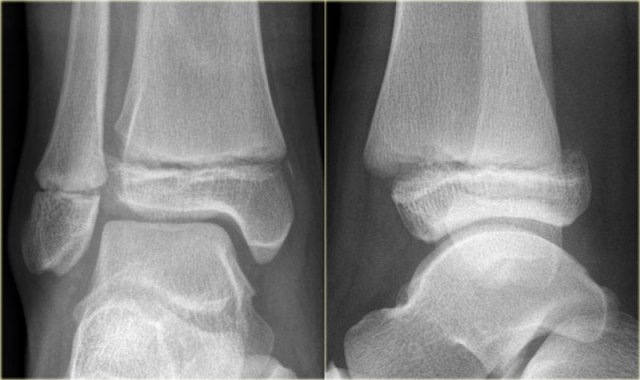

Example 2

• First impression

There is a fracture of the posterior malleolus.

Classification according to Weber is not possible.

An isolated fracture of the posterior malleolus is uncommon, but as part of a supination exorotation (Weber B) or pronation exorotation injury (Weber C) it is quite common.

So we have to re-examine the films to look for signs of a Weber B or C fracture.

• Re-examination

No sign of an oblique fracture of the lateral malleolus, so we can exclude a Weber B fracture.

There is still the possibility of a Weber C fracture, i.e. medial rupture or avulsion, high fibular fracture and finally a posterior malleolar fracture.

Now we notice the subtle avulsion of the medial malleolus (red arrow).

Additional radiographs of the lower extremity demonstrate a high fibular fracture (blue arrow).

• Final report

Weber C stage 4.